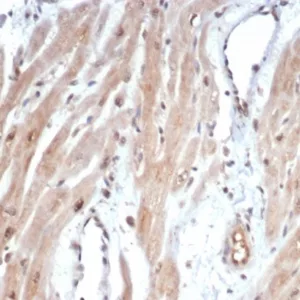

Antibodies against MYC are used in research to study its expression levels in cells and tissues. Immunohistochemistry, Western blotting, and chromatin immunoprecipitation (ChIP) techniques employing anti-MYC antibodies help researchers investigate its role in cancer and other diseases. Its expression is being explored as a potential prognostic marker in cancer.

Flow Cytometry, Immunofluorescence, Immunohistochemistry, Western Blot

Immunohistochemistry

Application:

Immunohistochemistry, Western Blot